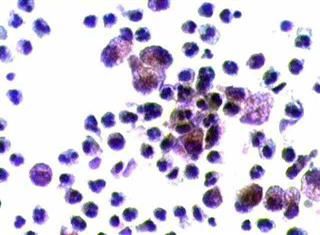

Aσθενής 45 ετών, με γνωστή παρουσία πολλαπλών κύστεων και στους δύο μαστούς εδώ και πολλά χρόνια.. Επώδυνη κύστη διαμέτρου 4 εκ. στον αριστερό μαστό. Κάτω από υπερηχογραφικό έλεγχο παρακέντηση και αφαίρεση περίπου 20 κ. εκ. κιτρινωπού υγρού.

Kύτταρα τοιχώματος κύστης μαστού. Αφρώδη κύτταρα, άφθονα πολυμορφοπύρηνα

Άμεση χρώση στεγνών παρασκευασμάτων, χωρίς μονιμοποίηση, κατά Papanicolaou και με  bleu de methylen.